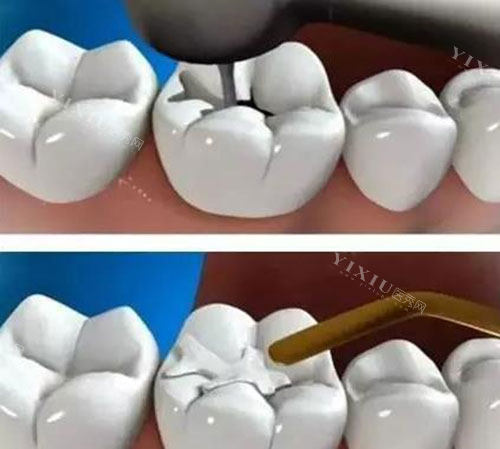

普通树脂补牙是台州多数口腔机构的基础项目,适合牙齿浅龋、小面积缺损的修复。其价格主要受材料品牌和机构定位影响,具体参考如下:

三、台州嵌体补牙价格表:大面积缺损,更准一些修复之选

当牙齿龋坏面积较大(超过牙面 1/3)或传统补牙易脱落时,嵌体补牙是更优选择。台州嵌体补牙价格根据材料和工艺差异,具体如下: